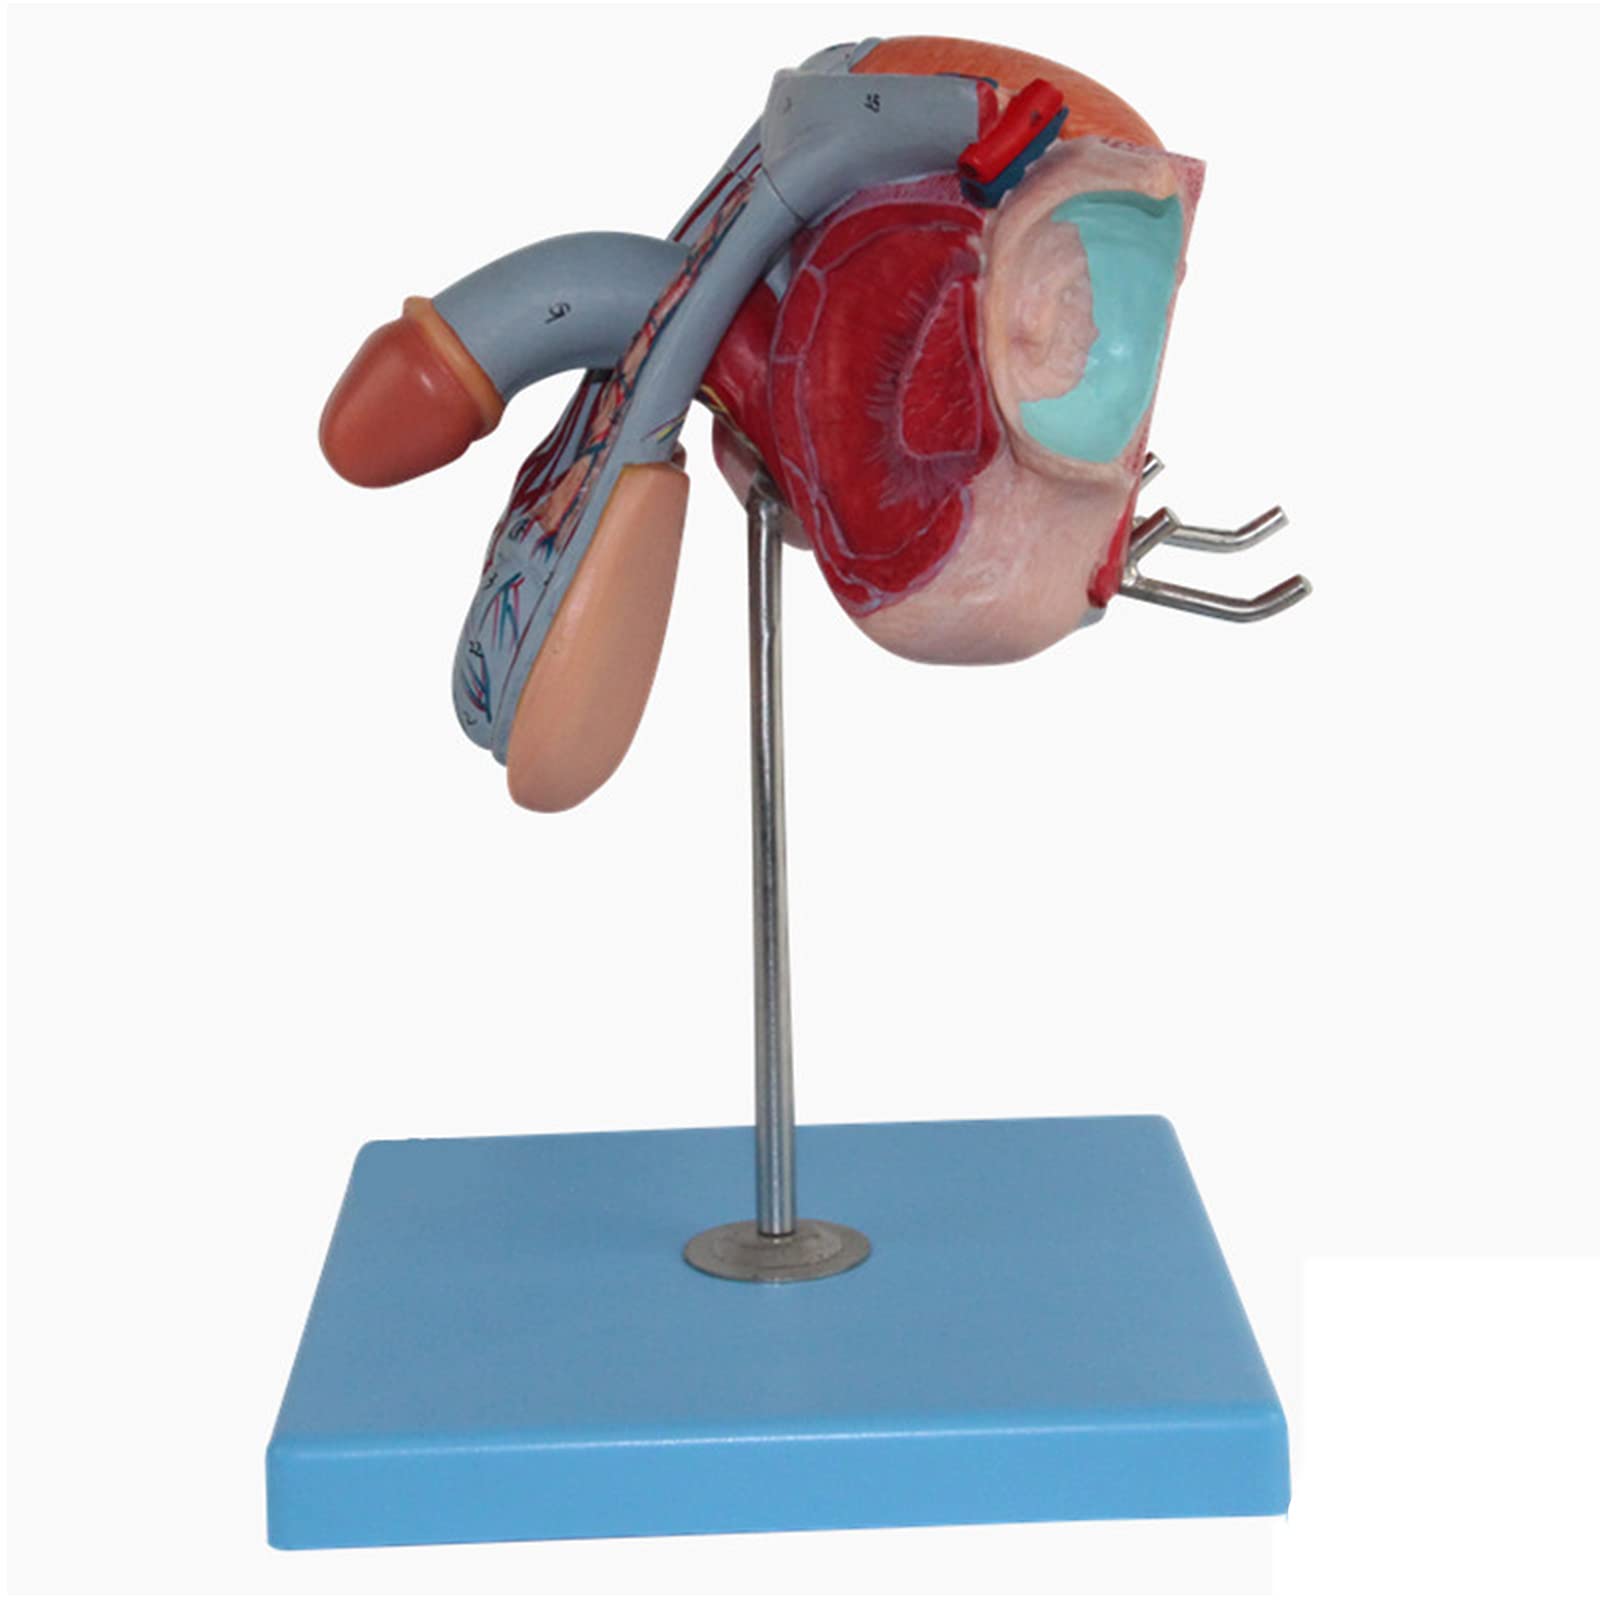

The Male Reproductive Model is a meticulously crafted anatomical aid featuring five detailed parts, including male genital organs and bladder sections. Made from durable, eco-friendly PVC, this model is designed for educational excellence, making it an ideal tool for schools and hospitals to enhance understanding of human anatomy.